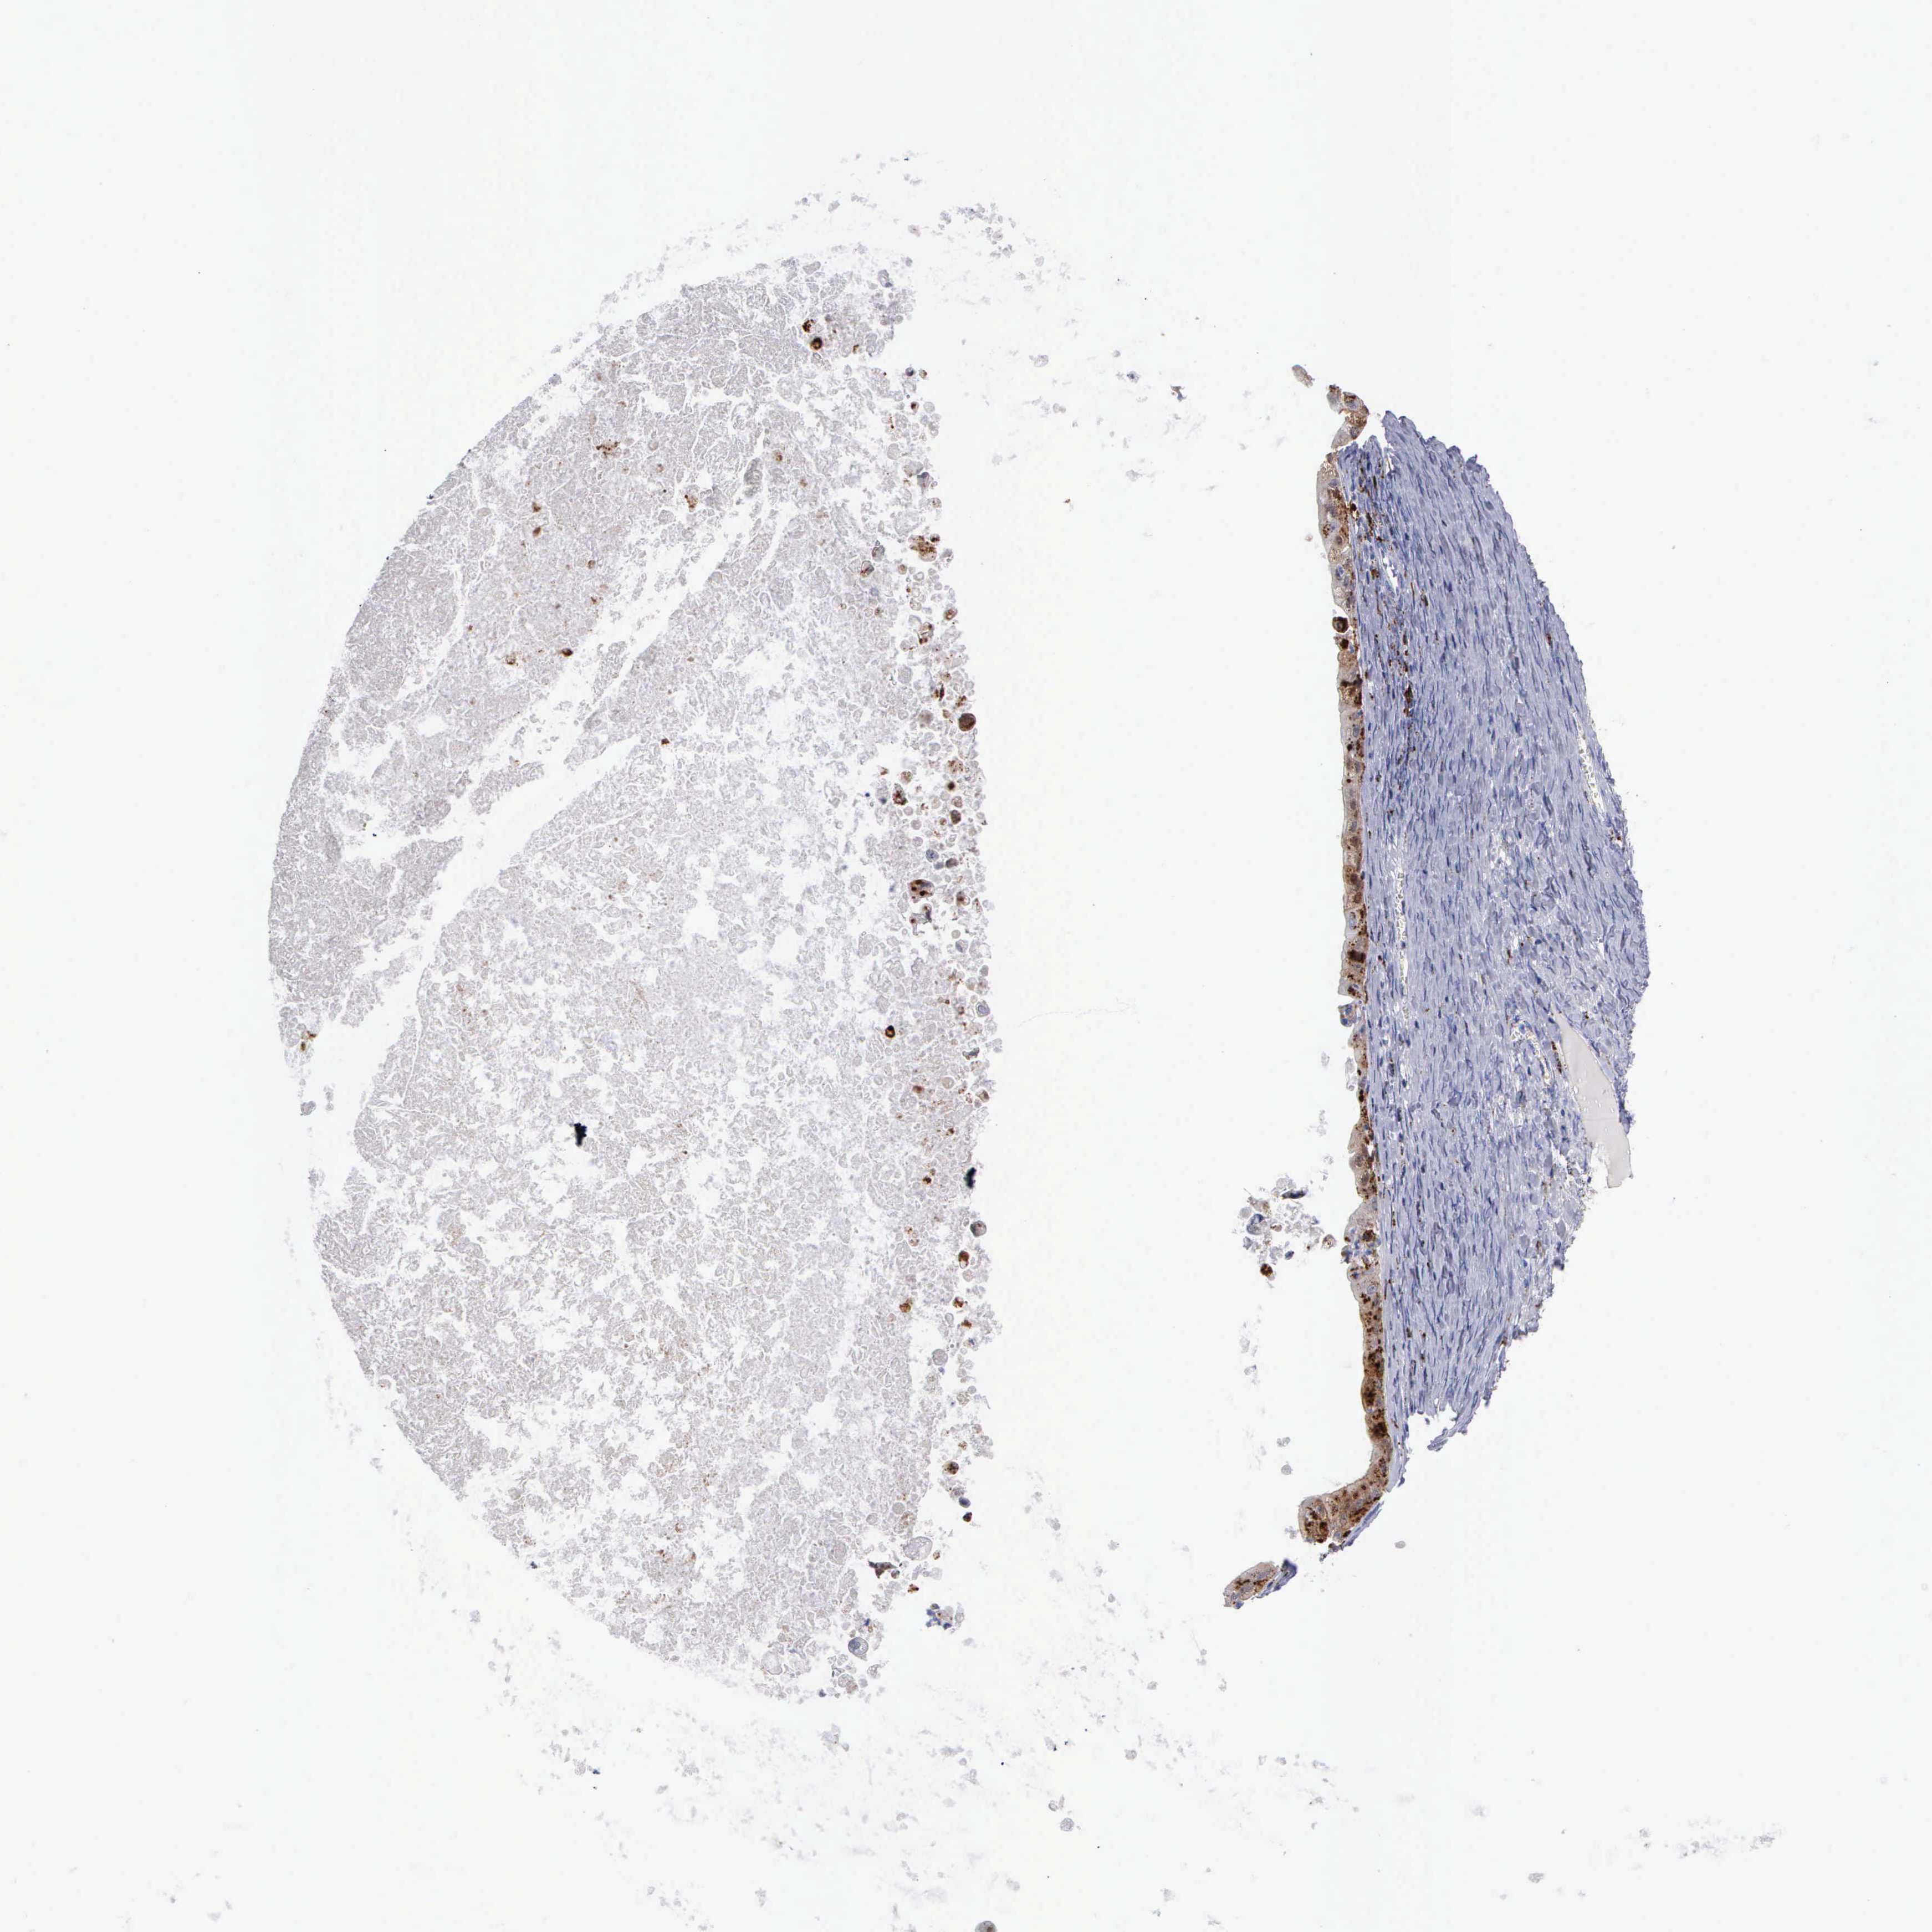

OVARIAN CANCER - Protein expressioni

A mouse-over function shows sample information and annotation data. Click on an image to view it in a full screen mode. Samples can be filtered based on level of antibody staining by selecting one or several of the following categories: high, medium, low and not detected. The assay and annotation is described here.

Note that samples used for immunohistochemistry by the Human Protein Atlas do not correspond to samples in the TCGA dataset.

Antibody stainingi

Antibody staining in the annotated cell types in the current human tissue is reported as not detected, low, medium, or high, based on conventional immunohistochemistry profiling in selected tissues. This score is based on the combination of the staining intensity and fraction of stained cells.

Each image is clickable and will lead to virtual microscopy that enables deeper exploration of all samples and also displays staining intensity scores, fraction scores and subcellular localization as well as patient and tissue information for each sample.

Antibody HPA003524

Antibody CAB000458

Cystadenocarcinoma, mucinous, NOS

Carcinoma, endometroid

Cystadenocarcinoma, serous, NOS